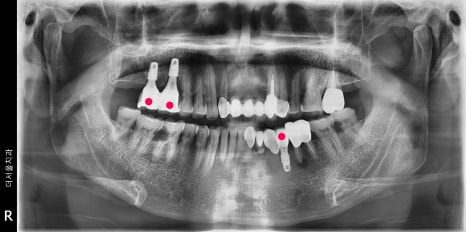

좌 : 1차 op, 우 : 2차 op 및 final

미리 결과를 예측했으니, 엑스레이에서

볼 수 있는 것 처럼 네비게이션 임플란트 3개를

심는데는 15분 채 걸리지 않습니다.

그 후에는, 대략 2~3개월 가량의 휴식기를

거치게 되면서 골 화를 기다리게 됩니다.

뼈와 다 아물게 되면, 오른쪽 사진에서

보실 수 있는 것 처럼 지르코니아 크라운이

연결이 되면 모든 시술은 끝나게 됩니다.